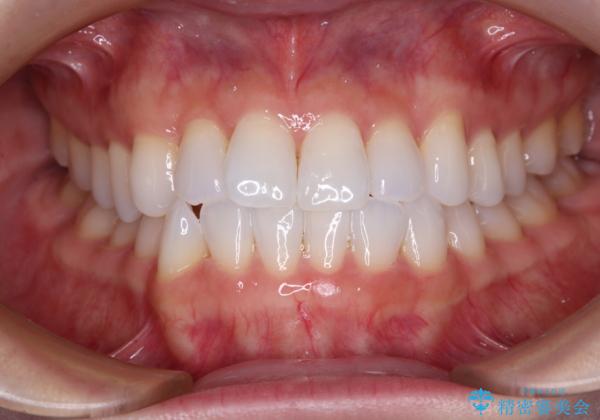

前歯のデコボコをインビザラインで綺麗に

- 上下前歯の叢生を気にして来院された患者様です。

インビザラインでの治療を希望されていて、デコボコの程度が中等度であり、安価なパッケージにて対応可能と判断されたため、インビザライン・モデレートを用いて矯正治療を行うこととしました。

インビザライン・モデレートは、製作できるアライナーの枚数に制限があるため、移動可能な量に限りがあるものの、インビザライン・ライトよりも枚数が多いため、幅広い症例に対応可能です。